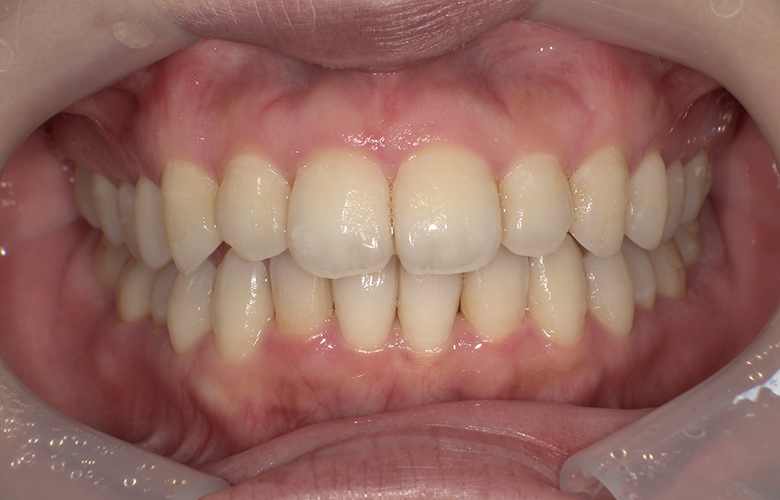

治療後 ![]() |

できるだけ目立たない治療を希望されたため、マウスピース型矯正装置を用いた治療をご提案しました。歯列のスペース確保のためにIPR(歯と歯の間の微小削合)を併用し、歯の移動量をコントロールしました。非抜歯で歯列を整えることで、自然な歯の形態を保ちながら審美性の改善を図りました。 |

前歯の重なりが解消され、歯列全体のバランスが整いました。見た目の改善により口元の印象が自然で明るくなり、清掃性も向上しています。咬合も安定しており、長期的な維持が期待されます。現在は保定装置を使用し、後戻り防止を行っています。 |

約9か月 |

約10回 |

約60万円 ※症例により変動あり |